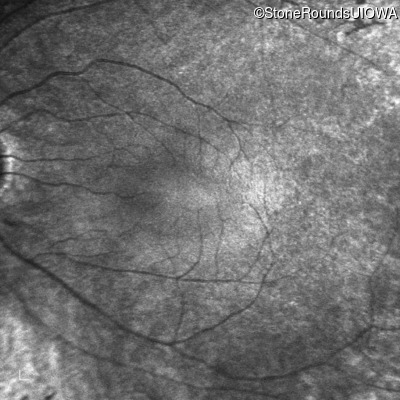

Infrared Fundus Photograph - Left - 20/80 -1

Exemplar